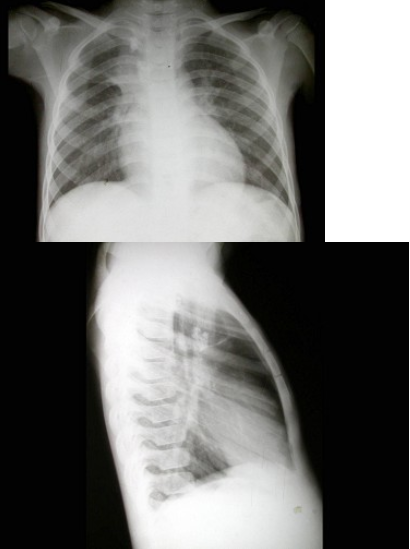

127、单项选择题

男,27岁,近2月来感胸闷,无咳嗽咳痰,不发热,X线检查如图,最可能的诊断是()

A.右侧包裹性胸腔积液

B.右侧肺不张

C.右侧游离性胸腔积液

D.右侧膈下脓肿

E.胸膜间皮瘤